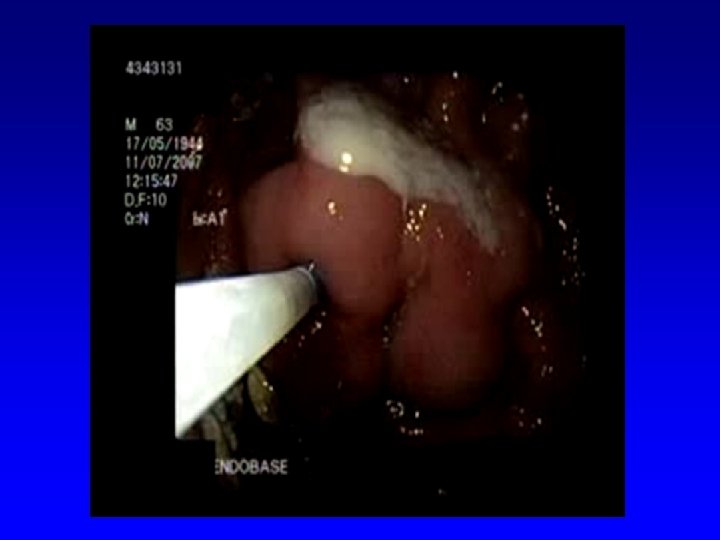

PHG: Portal Hypertension Gastropathy �The diagnosis of PHG is made endoscopically

Esophageal Varices Sclerotherapy Top Left: large varix with red color sign in lower esophagus Top Right: injection sclerotherapy using sclerosant with contrast medium. Right: Ulcers / erosions / adhesion are very common post sclerotherapy Prof. Dr. Abdel Fattah Hanno - Portal Hypertensive Gastropathy & Rebamipide

Esophageal Varices Band Ligation Gastroscopy image of esophageal varices with prominent red wale spots Esophageal varices seven days post banding, showing ulceration at the site of banding. Prof. Dr. Abdel Fattah Hanno - Portal Hypertensive Gastropathy & Rebamipide